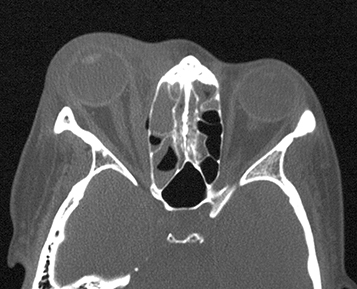

(See Figures 7.3.1.1 and 7.3.1.2.)

Eyelid edema, erythema, warmth, and tenderness. Conjunctival chemosis and injection, proptosis, and restricted extraocular motility with pain on attempted eye movement are usually present. Signs of optic neuropathy (e.g., afferent pupillary defect and dyschromatopsia) may be present in severe cases.

Decreased vision, retinal venous congestion, optic disc edema, purulent discharge, decreased periorbital sensation, and fever. CT scan usually shows adjacent sinusitis (typically at least an ethmoid sinusitis) and possibly a subperiosteal orbital collection.

Imaging: CT scan of the orbits and paranasal sinuses (axial, coronal, and parasagittal views, with contrast if possible) to confirm the diagnosis and to rule out a retained foreign body, orbital or SPA, paranasal sinus disease, cavernous sinus thrombosis, or intracranial extension. If superior ophthalmic vein or cavernous sinus thrombosis are suspected clinically, MRI with contrast and fat suppression should be obtained.

Obtain CT with contrast, which allows for easier identification and extent of an abscess. In cases of suspected cavernous sinus thrombosis, discuss with the radiologist before CT, since special CT techniques and windows may help with diagnosis. MRI may also be indicated in cases of cavernous sinus thrombosis, skull base spread of infection and meningitis.